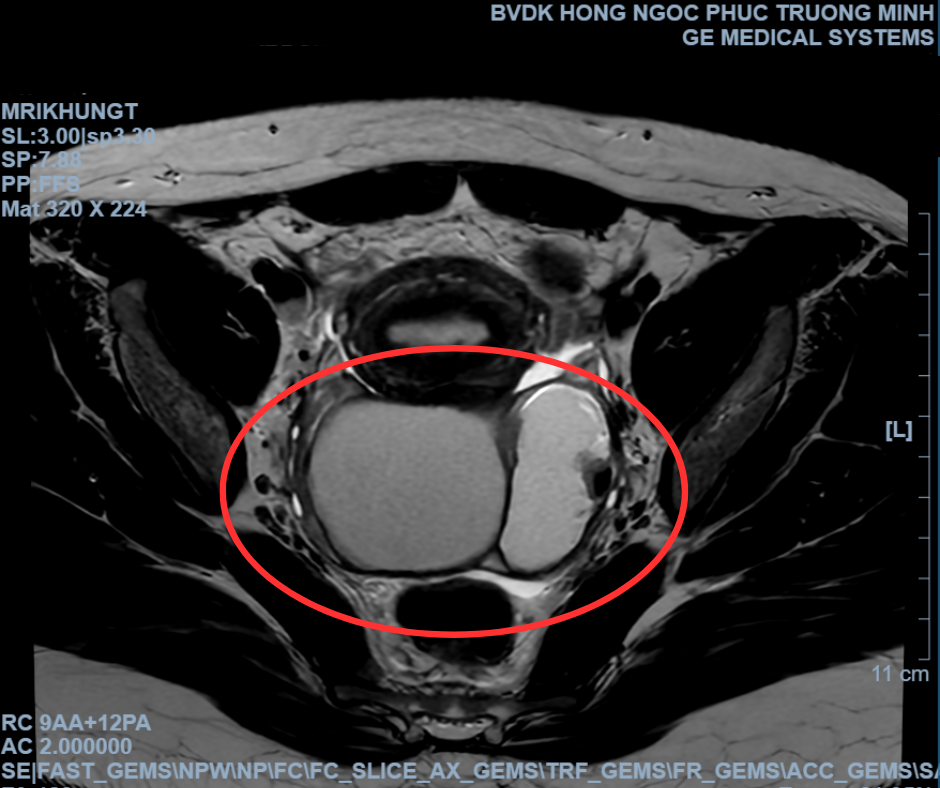

Bệnh nhân N.T.T (22 tuổi, Hà Nội) đến Bệnh viện Đa khoa Hồng Ngọc kiểm tra sức khỏe trong tình trạng bụng dưới đau âm ỉ và sốt nhẹ. Qua thăm khám, các bác sĩ kết luận bệnh nhân bị viêm phần phụ 2 bên, đặc biệt tình trạng viêm dính đã lan rộng nghiêm trọng hình thành các ổ mủ và áp xe. Thêm vào đó, tại buồng trứng trái của bệnh nhân cũng có khối u nang bất thường với kích thước lớn, chèn ép các cơ quan xung quanh.

Hình ảnh siêu âm cho thấy khối áp xe mủ và u nang buồng trứng.